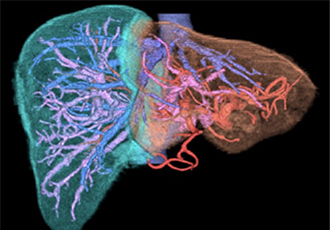

Ⅰ.肝胆膵疾患の画像診断

造影超音波、64列のMD-CT、1.5TのMRI、コーンビームCT付きの血管造影装置による最新の画像診断が随時施行可能です(図1)。加えて肝臓手術には必須の3次元画像解析システムボリュームアナライザー SYNAPSE VINCENT™による血管の3次元画像の構築や肝臓の切除体積評価が可能になりました(図2)。

図2 VINCENTによるシミュレーション画像

肝臓や脈管の3次元的な描出が可能です。

肝臓の門脈がピンク色に、肝静脈が青色に、肝転移巣が緑色に描出されています (A)。

さらに肝切除予定領域が緑色と黄色で示されています (B)。

• シミュレーション画像:肝臓の門脈がピンク色に、肝静脈が青色に、肝転移巣が緑色に描出されている

• シミュレーション画像:肝切除予定領域が緑色と黄色で示されている